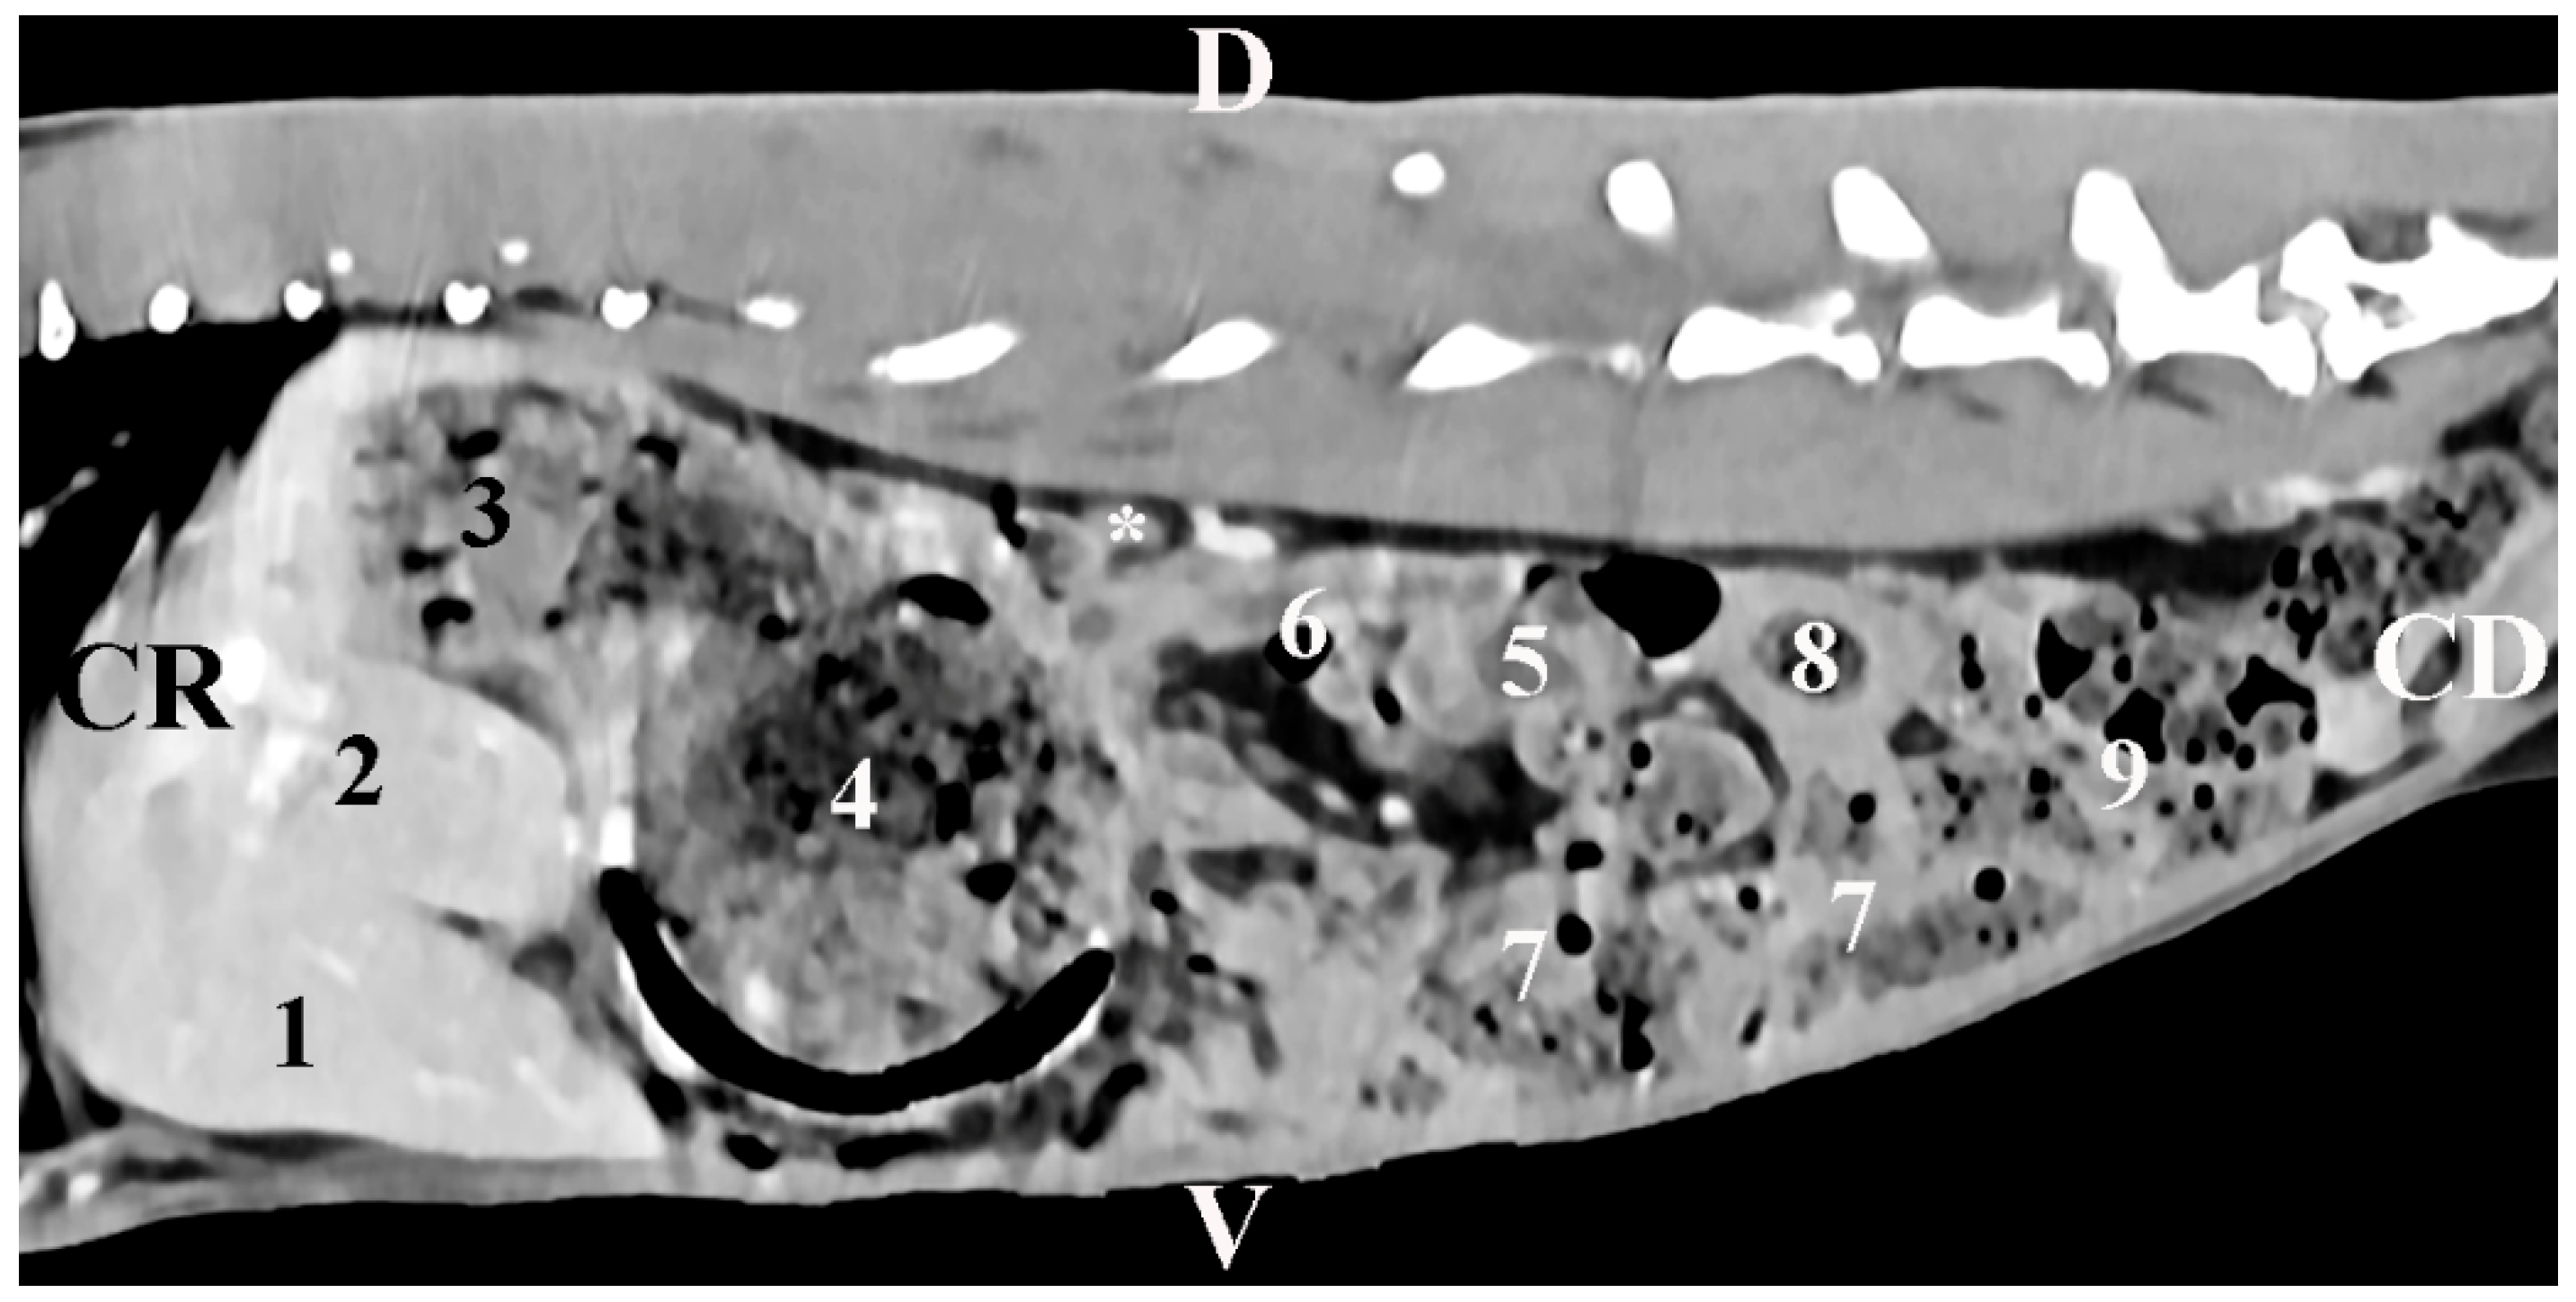

The sagittal post-contrast CT scan of regio abdominis 10 mm left to the spine showed the image of the gl. adrenalis sinistra. The gland was retroperitoneally located in the regio abdominis lateralis sinistra. The left adrenal gland was a soft tissue finding with intermediate density. The gland was observed close to the contrast-enhancing aorta abdominalis and the stomach. It was at a distance from the left kidney. The gland had an oval shape and distinct borders. The spinal muscles remained dorsal to the gland (Figure 4).

Figure 4. Sagittal CT post-contrast anatomical study of the rabbit abdomen at the level of the plane at 10 mm to the left of the spine. CR—cranial; CD—caudal; D—dorsal; V—ventral. (white star) mesenterial fold; (1) lobus hepatis sinister lateralis; (2) lobus hepatis sinister medialis; (3) fundus ventriculi; (4) corpus ventriculi; (5) left kidney; (6) pars ascendens duodeni; (7) caecum; (8) colon ascendens; (9) jejunum.